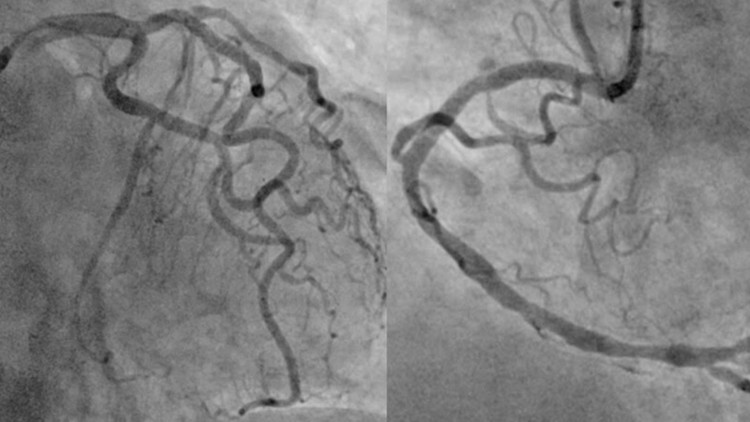

Sau khi giải thích kỹ chẩn đoán, định hướng điều trị, các lợi ích và nguy cơ của thủ thuật cho người nhà, người bệnh lần lượt được can thiệp nong bóng và đặt stent thành công cả ba nhánh động mạch mũ, động mạch liên thất trước và động mạch vành phải. Người bệnh sau đó được chuyển lên khoa Hồi sức tích cực – Chống độc để tiếp tục điều trị.

Hình ảnh mạch vành của người bệnh sau khi được can thiệp tái thông toàn bộ các động mạch vành tắc và hẹp. Ảnh BV